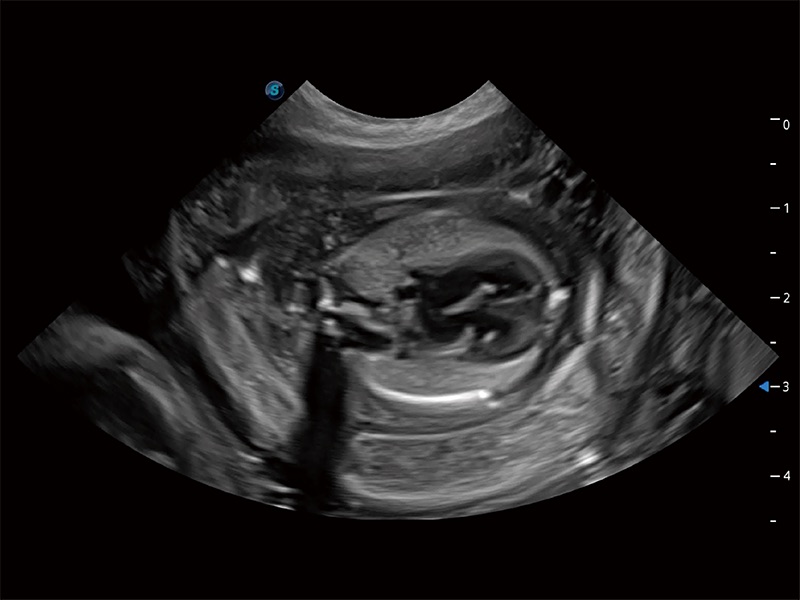

高性能和先进的临床应用工具可以为动物医生提供临床信心。ProPet 80 搭载了先进的腹部和浅表应用工具,帮助医生在日常临床实践中发挥前所未有的作用。

ProPet 80 配备了丰富的心脏探头群、先进的成像技术和专业的心脏测量工具,可帮助动物医生为不同体型和生理结构的动物提供心脏和心肌功能的全面评估。

ProPet 80 专为动物医生设计,对不同的动物体型和生理结构作出了针对性的优化。通过动物影像专用软件,可满足个性化的应用需求,帮助动物医生获得更精确的诊断数据。

ProPet 80 全新的动物超声智能软件和丰富的探头群,为动物医生提供了高清晰度和精细分辨率的图像,无论在宠物、马科、畜牧还是实验室动物等应用中都可以轻松应对,为您的日常工作带来满意的体验。